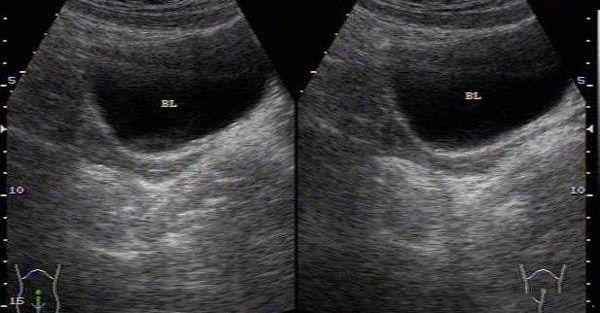

B超下的幼稚子宫

首先幼子子宫又叫幼稚子宫,是子宫发育不良的一种,主要指子宫结构和形态正常,但体积较小,子宫颈相对较长,是当下困扰不少女性生育的重要原因之一。

虽然说幼稚子宫对于女性的生育有着很大的影响但也并非是不能生育宝宝,一般会分为先天性幼稚子宫和后天发育不良性小子宫,如果是后者,只会降低受孕率,并非绝对不孕的指征。如果是前者,是很难怀得上孕的那么做试管婴儿意义也不大。